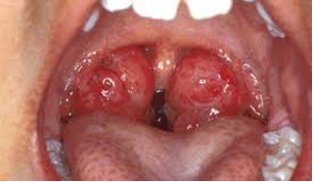

Khi vi khuẩn ồ ạt xâm nhập và tấn công mũi họng, amidan phải chống lại quá mức dẫn đến tình trạng viêm sưng, đỏ. Hậu quả là tại amidan sẽ tập trung các “xác” vi khuẩn và “xác” bạch cầu, mô hoại tử hình thành các cục mủ rất hôi. Khi amidan bị viêm nhiều lần, khả năng chống chọi với vi khuẩn bị yếu đi. Lúc này, chính các ổ viêm nằm trong amidan lại là nơi khởi phát cho những đợt viêm vùng họng. Viêm amidan chiếm tỷ lệ cao ở trẻ em, thường do vi khuẩn gây ra.

- Dùng đè lưỡi đè vào 2/3 trước lưỡi thấy toàn bộ niêm mạc họng đỏ rực, tăng xuất tiết, amidan sưng to và đỏ, trụ trước và trụ sau nề đỏ, nếu kèm các triệu chứng viêm long đường hô hấp trên như chảy nước mắt, nước mũi, xung huyết củng mạc mắt thì nguyên nhân thường gặp do virus.

- Trường hợp do nhiễm khuẩn sẽ thấy trên bề mặt amidan có nhiều chấm mủ ở các khe, có khi thành đám như giả mạc, lấy ra dễ dàng, tan trong nước.